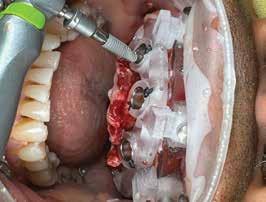

72 FDC 2026 Speaker: Full Arch Implant Reconstruction in the Digital Era: Past, Present and Future